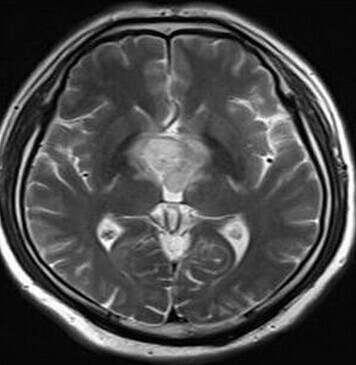

第三脑室脊索样胶质瘤

患者:男,50岁,记忆力下降1月余,双眼视力下降,反应减慢。

【正确答案】D 胶质瘤(第三脑室脊索样胶质瘤)

第三脑室脊索样胶质瘤的特征性表现是:

(1)见于成人,边界清楚,位于第三脑室前部;

(2)T1WI上为低信号,T2WI上呈明显高信号;

(3)增强后明显强化;

(4)肿块累及视交叉及下丘脑,但不浸润周围脑实质。